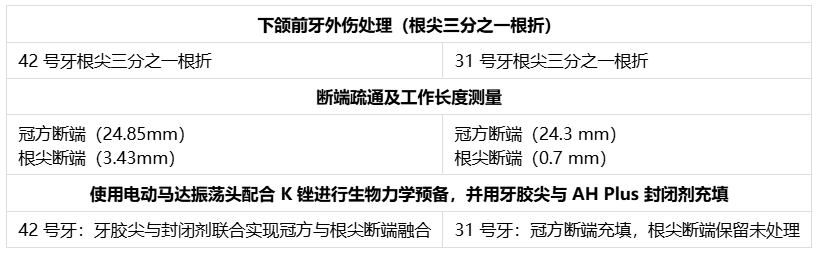

图4. 下颌前牙创伤处理(根尖三分之一根折)

具体方法如下:初级技术中,31号牙保留根尖断端。首先对疼痛更明显的31和41号牙安排根管治疗。使用利多卡因(1:80000)麻醉,橡皮障隔离。为两颗中切牙开髓,用圆钻和Endo Z钻制备三角形髓腔入口。去除牙髓,使用6K、8K、10K、15K锉初步疏通,建立滑行通路。通过数字化放射片及根尖定位仪确定工作长度(31号牙25毫米,41号牙24毫米)。使用润滑剂(乙二胺四乙酸凝胶)配合2.5%次氯酸钠与生理盐水交替冲洗,将根管扩大至30K。使用K锉进行生物力学预备,配合电动马达手机振荡头。初诊时放置氢氧化钙封药。复诊时使用牙胶尖和AH Plus封闭剂(Dentsply)进行充填。采用热垂直加压技术,使用快速充填笔操作。右下中切牙存在侧支开口及唇侧弯曲,根尖部可见封闭剂溢出。左下中切牙根管充填至冠方断端24.3毫米处,未触及根尖断端。根管治疗后使用玻璃离子水门汀(GIC)修复(图5A-5B)。

图5. A) 31和41号牙根管治疗,31号牙保留根尖断端(圆圈及蓝色箭头),42号牙根尖三分之一根折(红色箭头);B) 42号牙冠方断端疏通(黑色箭头);C) 42号牙根折线(圆圈);D) 42号牙根尖断端疏通(红色箭头);E) 42号牙冠方至根尖断端通路

第二种方法采用非手术方式对42号牙冠方与根尖断端进行对位。最初对42号牙采取观察策略,但因患者主诉不适、疼痛及牙齿松动加重,决定实施非手术根管治疗重新连接冠方断端。遵循COVID-19防护措施、患者知情同意及防护技术。对患者实施麻醉,橡皮障隔离。制备髓腔入口,去除冠方断端牙髓。使用25毫米K锉在冠方断端建立初步疏通及滑行通路。冠方断端疏通及预备采用K锉配合电动马达手机振荡头(NSK)。首先仅预备冠方断端,建立直线通路,放置氢氧化钙封药。保留弯曲的根尖断端。三天后患者根管疼痛复发,药物治疗无效。再次检查放射片,推测根尖三分之一断端残留牙髓可能是疼痛持续原因。使用31毫米锉疏通根尖断端,采用直线通路进入牙根冠方至根尖断端。采用平衡力技术冠向下预备确保成形。通过根尖定位仪及影像学分析确定工作长度,使用根管测量尺测量。该牙工作长度约28.30毫米(图6)。